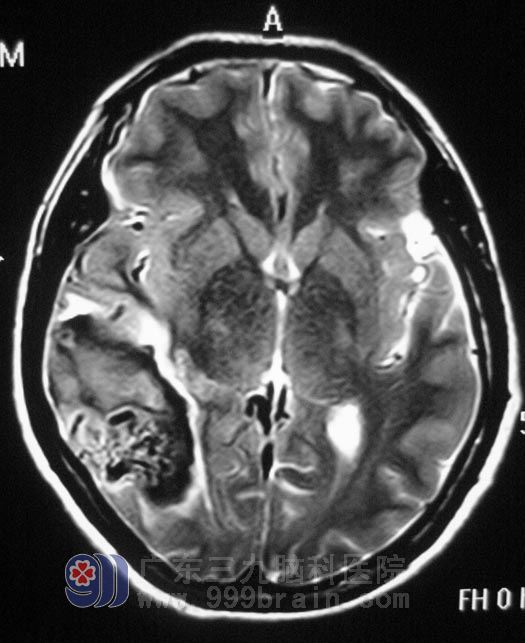

杨老师在一所小学教音乐,5月6日晚上10点左右,突然出现头晕、头痛伴恶心,没有呕吐,双手紧握;当时神志清醒,休息后无好转,第二天在当地医院就诊,头、颈部CT发现:脑右侧颞叶出血,可见钙化,考虑动静脉畸形,由于当地的医疗技术设备有限,同时也不能排除有二次出血,立即转到了广东三九脑科医院综合神经外科。

▲手术前